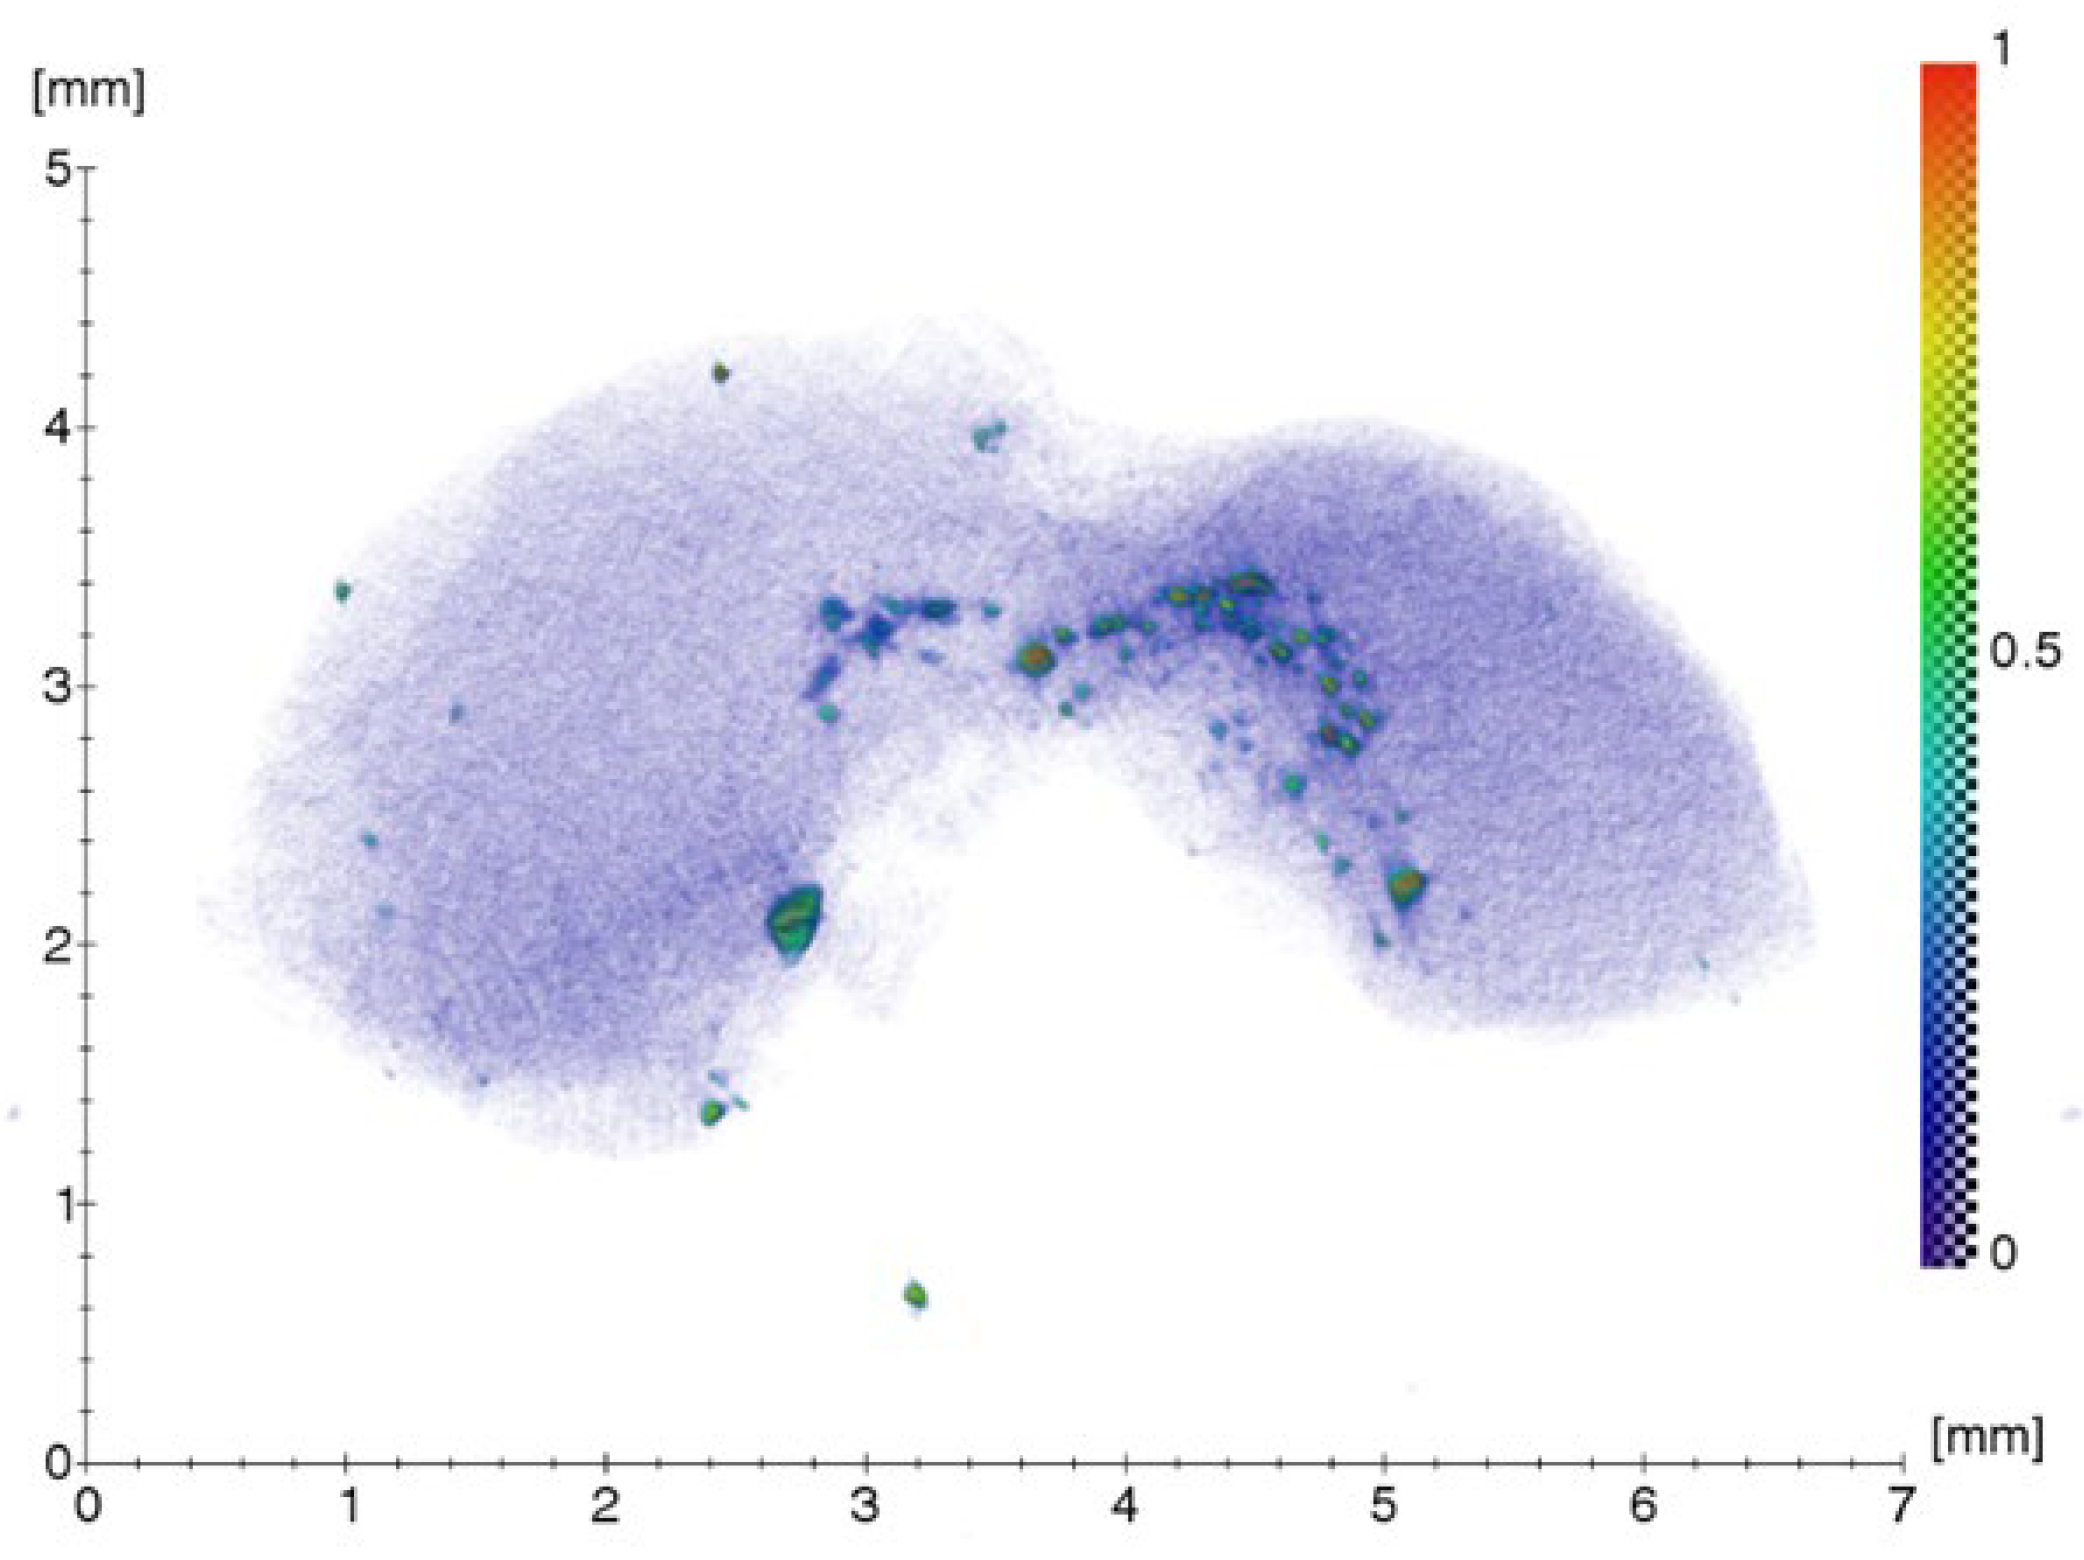

2.1. Results of Clinical Case Investigation

2.1.1. Results of X-ray and Electron Microscopic Studies

4.2. X-ray Microtomography (XMCT)